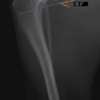

本症例は、走った後に左後肢を挙上していることを主訴に来院されました。触診時に左膝関節のクリック音を聴取、レントゲン検査にて左脛骨の前方変位が認められました。術中に、前十字靱帯の断裂及び内側半月板の損傷、内側の軟部組織の顕著な腫脹を確認。半月板切除、TPLOを実施しました。周囲組織への炎症の波及もあったため回復に時間を要しておりますが、徐々に跛行頻度は減少傾向にあり、現在も経過観察中です。術前に約29°あったTPAは術後に約10°まで矯正されました。

術前写真

手術前後のTPA(脛骨高平部の角度)を測定しています。

約29°から約10°へ矯正されています。